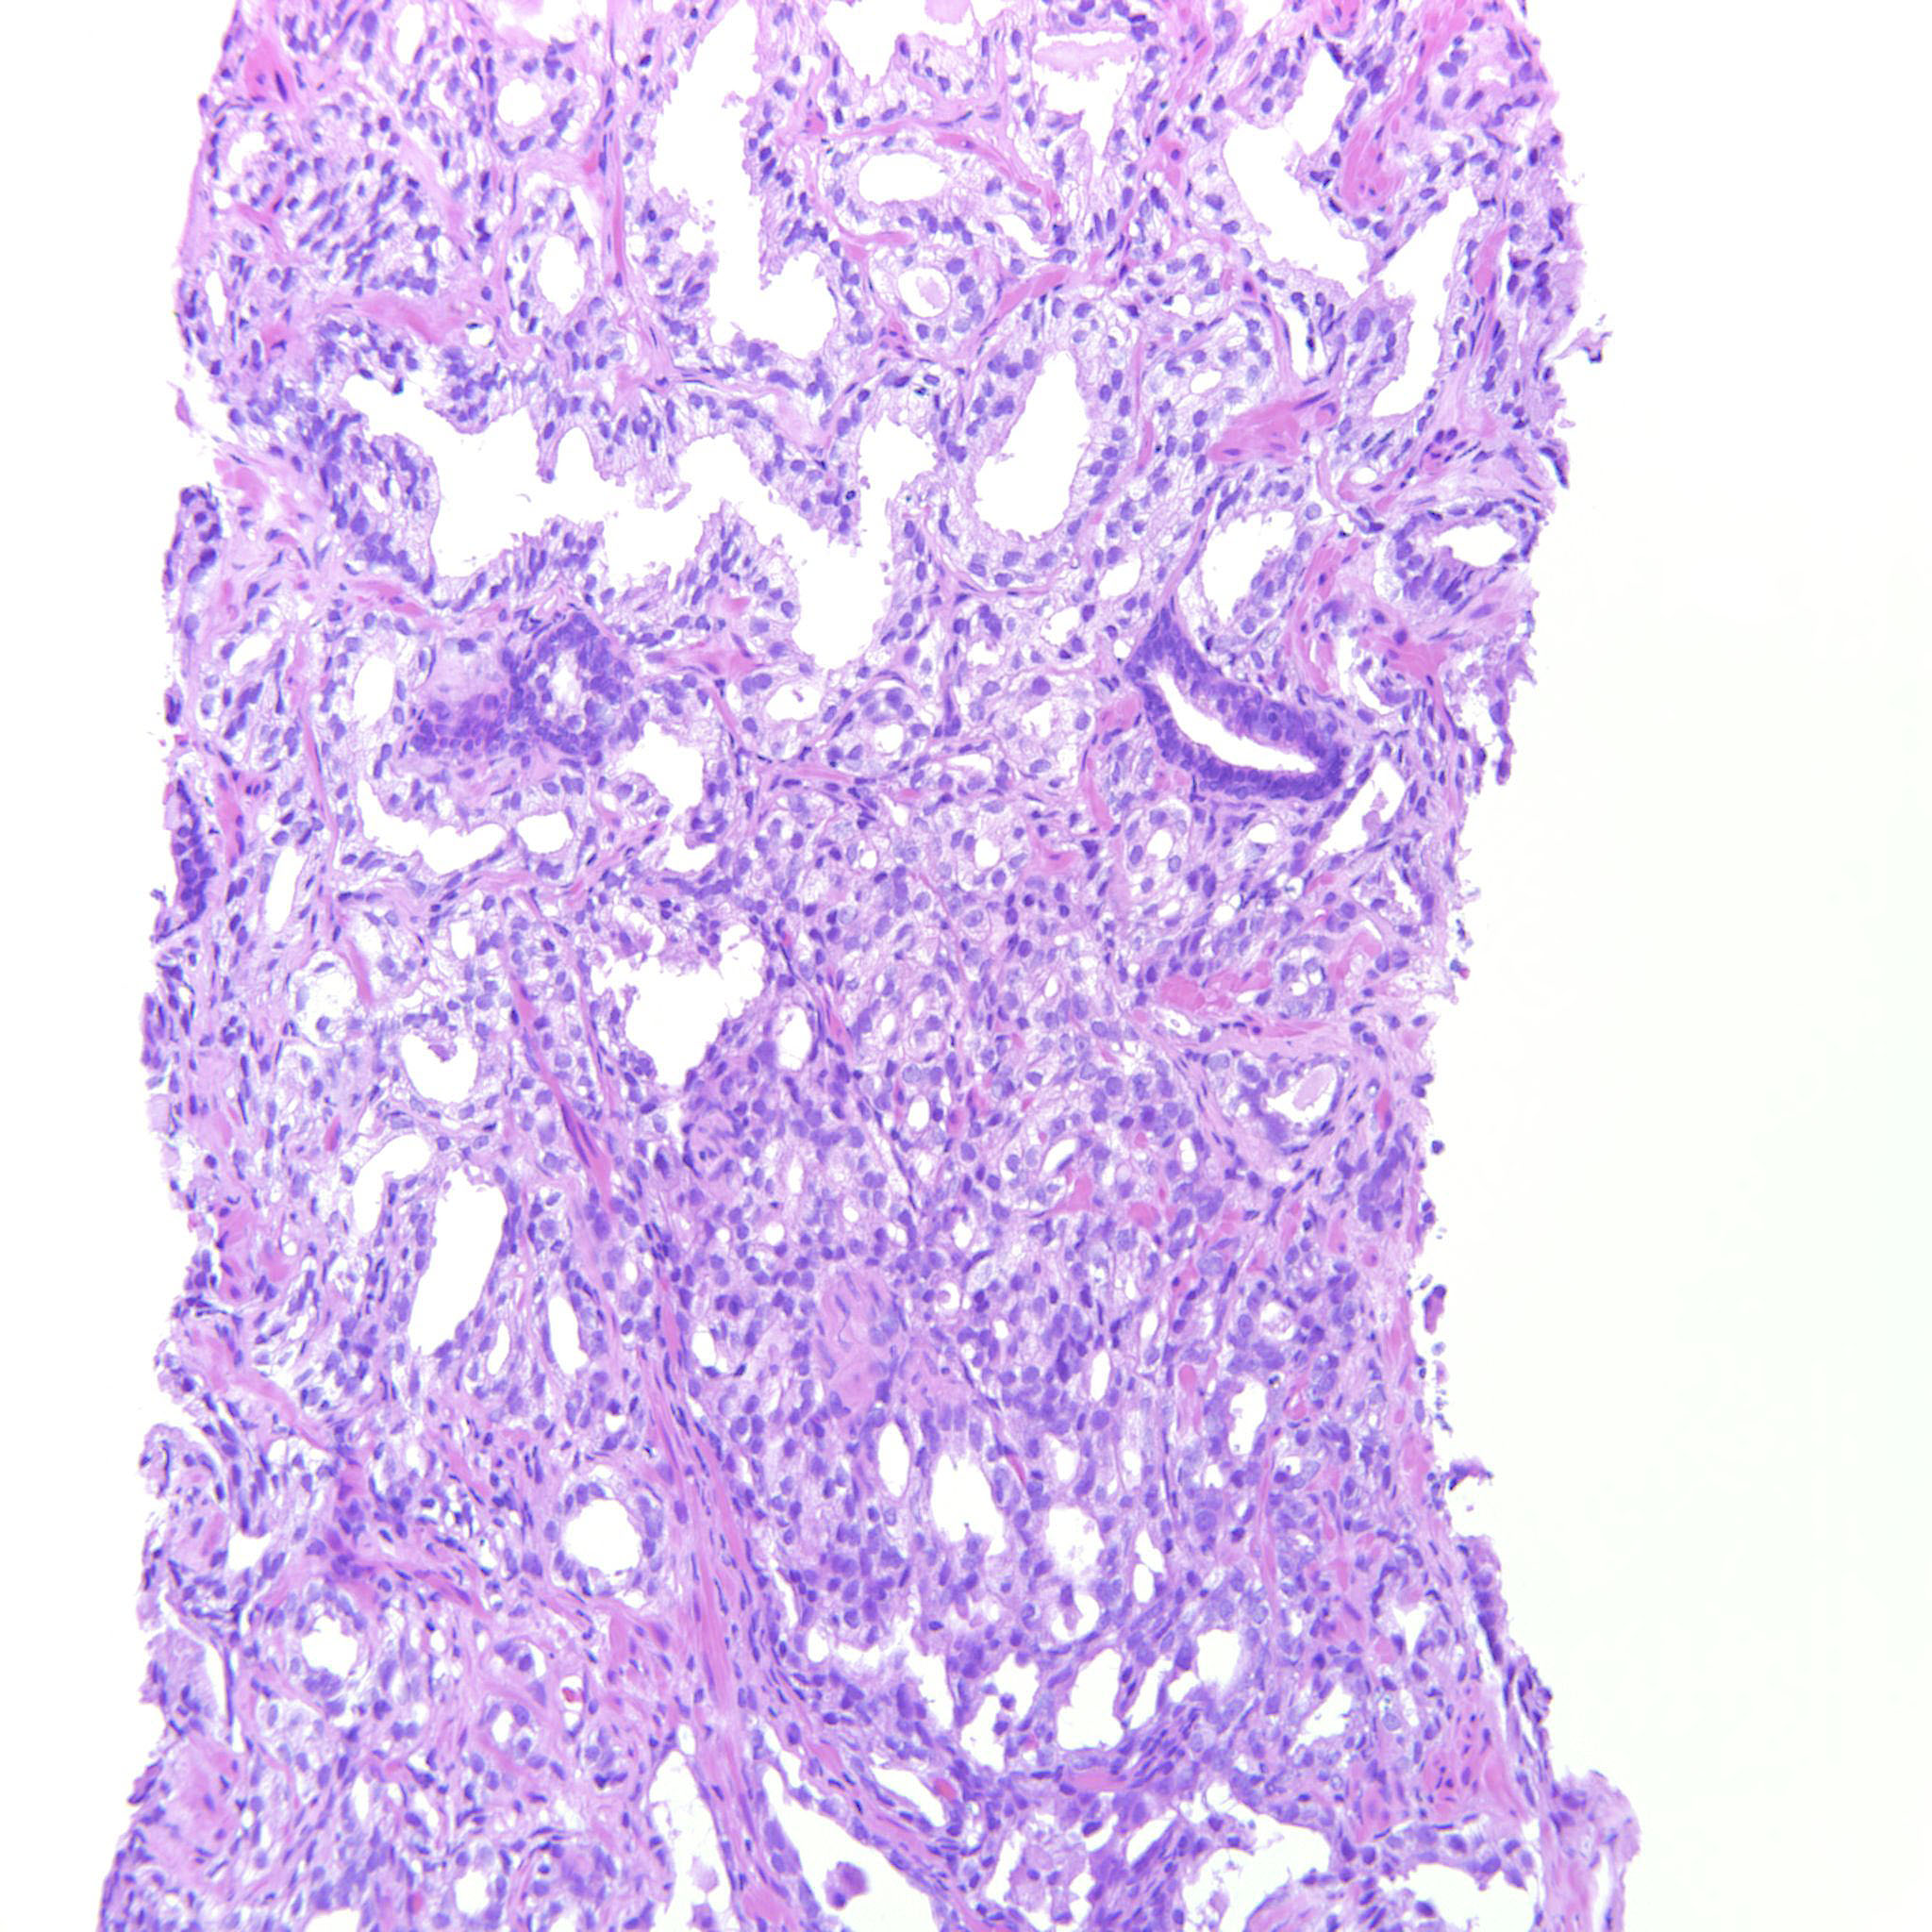

Prostate cancer grading

Case ID: 322